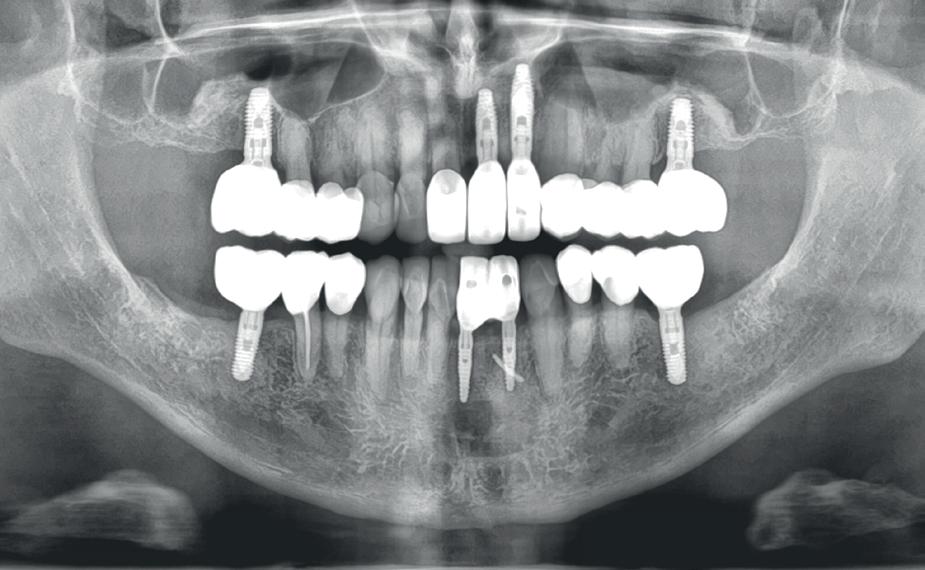

De diagnose luidde lokaal parodontitis met ernstige furcatie aandoeningen; Stadium IV (vergevorderd); graad C (snel progressief) (afbeelding 7) De elementen die niet te behouden waren, werden geëxtraheerd.

5. OPT intake

6. OPT na infectie controle

10. OPT-implantaten

9). In de bovenkaak werd bilateraal een sinuslift uitgevoerd. Aansluitend werden in beide kaakhelften implantaten geplaatst (afbeelding 10).